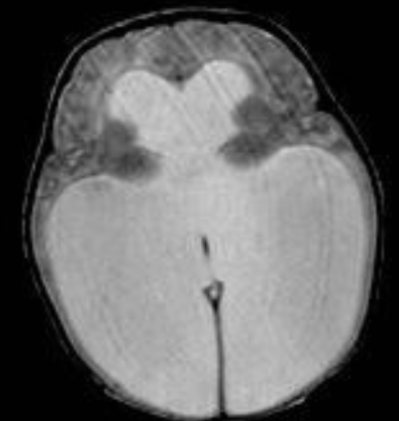

• Cause des hydrocéphalies non-communiquantes

• absence de Flow de LCR

stenose aqueduc acqueduc acqueduct de slyvius